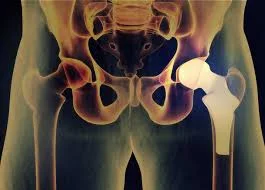

Modern hip replacement surgery is a well-established procedure that has benefitted from decades of research and development. It involves the removal of damaged or diseased hip joint components and their replacement with artificial implants. The surgery is typically performed under anesthesia, and patients can choose between traditional or minimally invasive techniques.

During the surgery, the damaged cartilage and bone are removed from the hip joint. Then, an artificial hip implant, consisting of a metal or ceramic ball attached to a stem and a socket with a liner, is securely fitted into the joint. This prosthetic hip joint replicates the natural movement of the hip, allowing for improved mobility and pain relief.